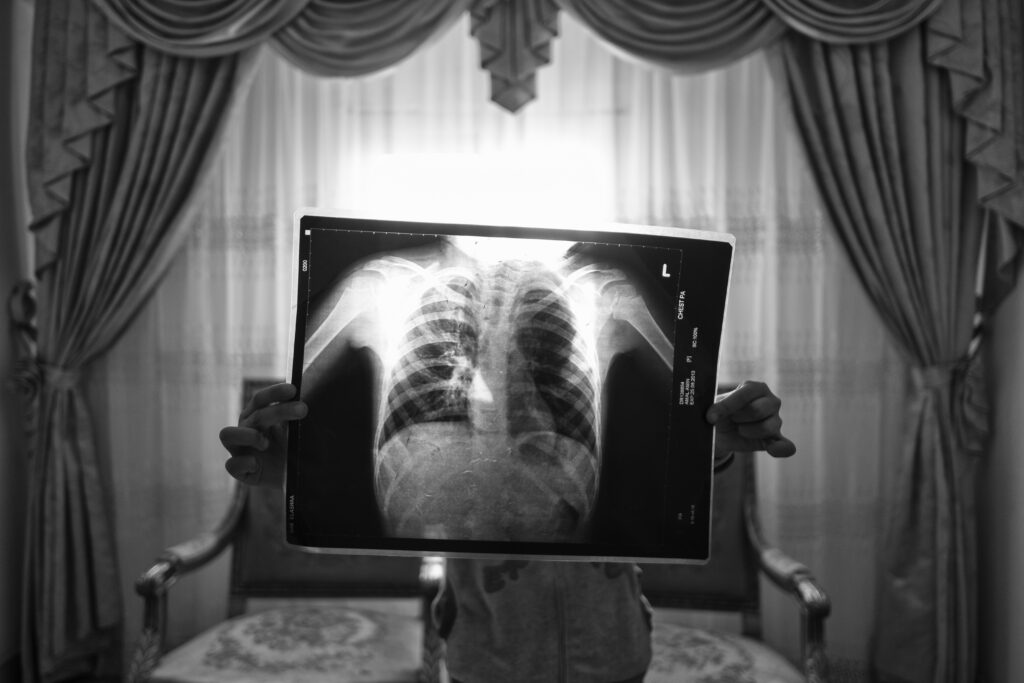

Crèdit: © Mohamed Mahdy, Arab Documentary Photography Program

Peu de foto: Amal sosté una radiografia dels seus pulmons. Es va traslladar a la Vall de la Lluna als tres anys i va desenvolupar asma en pocs mesos. Alexandria, Egipte, 31 de gener de 2018.

Història: Més de 30.000 residents de Wadi El-Qamar, coneguda com la Vall de la Lluna, a l’oest d’Alexandria (Egipte), viuen a menys de 15 metres d’una fàbrica de ciment que omple les seves llars de pols tòxica. Els infants neixen amb asma i les famílies pateixen malalties pulmonars i danys respiratoris irreversibles. El 2016, el fotògraf —que viu a prop i també pateix asma— va començar a documentar les seves històries i les lluites legals en curs.